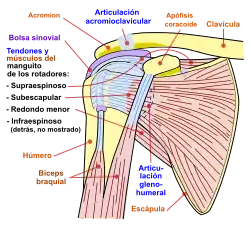

Diagrama de la articulación del hombro, vista frontal.

Diagrama de la articulación del hombro, vista frontal. -